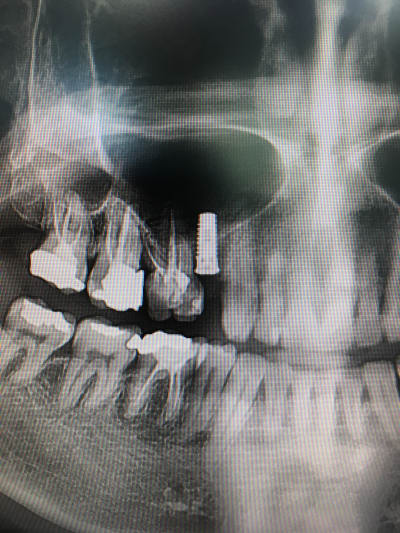

Bonjour chers confrères et consoeurs, j'ai besoin de votre aide pour identifier cet implant ( dentiste poseur en retraite, plus de dossier).

"la mesure" sur la rétro donne un diametre de 3.8 ou 4 et 10 de long .

j'en peux plus des captures d'écran merdiques au smartphone qui bouffent 50% des détails nécessaires à une bonne identification!!!

mais là pour l'instant je fais choux blanc (enfin disons plutôt que j'ai plusieurs pistes)...çà serait pas mal si tu pouvais faire une radio bien centrée sur l'implant que je puisse avoir un max de détails....

Qq'un m'a parlé de IDI mais l'extrémité apicale de l'implant parait plus plâte dans mon cas.

le truc qui colle le mieux, c'est un osstem SS3...mais j'ai des doutes....

je pencherai pour un Imax d'idi

http://www.idi-dental.com/fr/catégorie/connexion-hexagonale

http://www.idi-dental.com/fr/produit/idmax

Pas idiot du tout, ça matche pour le nb de spire avec l'illustration du site...

j'ai demandé à un pote qui pose du IDI.

ça reste qu'une illlustration et il n'est pas précisé de quel implant il s'agit (diam et lg ?)